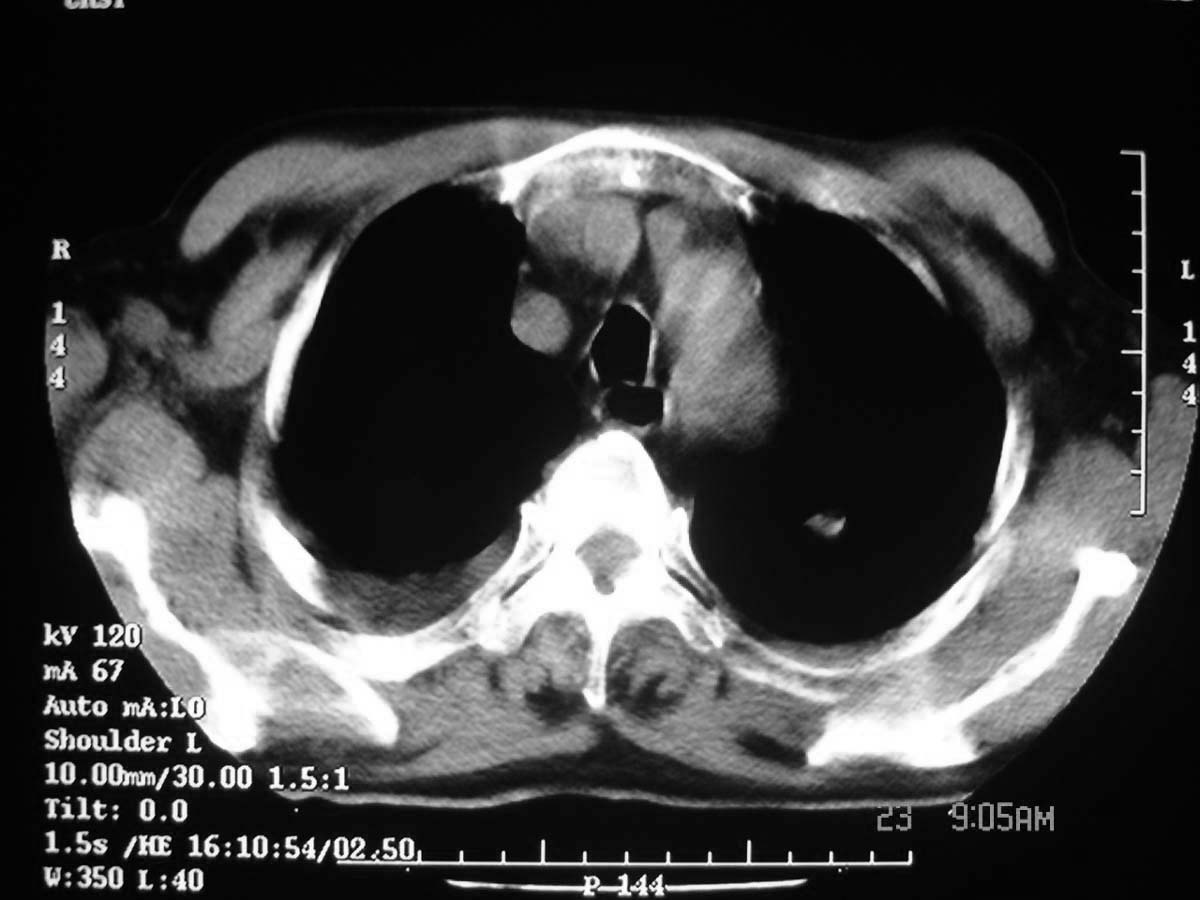

以下是引用守望可可西里在2006-11-23 14:33:00的发言:[br][br] 糖尿病病人很容易继发结核,病人又有双侧胸膜增厚、粘连、胸腔积液以及双上肺的斑片状、条索状影结核病灶影,以一元论考虑,右下肺病变首先考虑干酪性肺炎,可以正规抗炎治疗后复查,排除一般的肺炎。